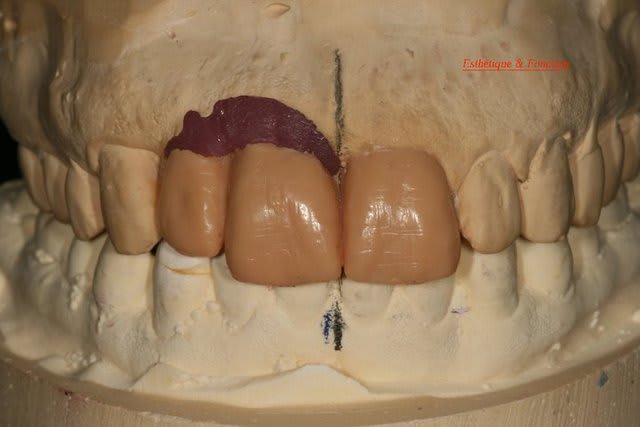

tu devrais faire faire par ton prothésiste un wax avec les dents en blanc et les tissus mous qu'il te manque en rouge afin de bien visualiser tous les tissus qu'il te manque.

Je mets quelques photos de la patiente au cab et du prothèsiste d'Epinal.

Ton protho pourrait maquiller un peu plus les provisoires et éviter les bulles......

Je suis persuadé que si ton prothèsiste réussit à reproduire la richesse des petits défauts de ses propres dents sur tes dents en céramique , ce serait et ça passerait bcp mieux

Je crois que finalement ces trois trop jaune et quasi monolithique ds leur couleur est vraiment la chose la plus atroce

Bon finalement je vous poste le cas terminé.

La prochaine fois je ferrai une greffe d'apposition comme j'avais pu le préssentir... Ca me permettra de garder les papilles.

A la prochaine séance je gomme la coloration mésiale de 12, c'est promis ;+)

Un cas pas évident... l'important est que la patiente soit contente à la fin.